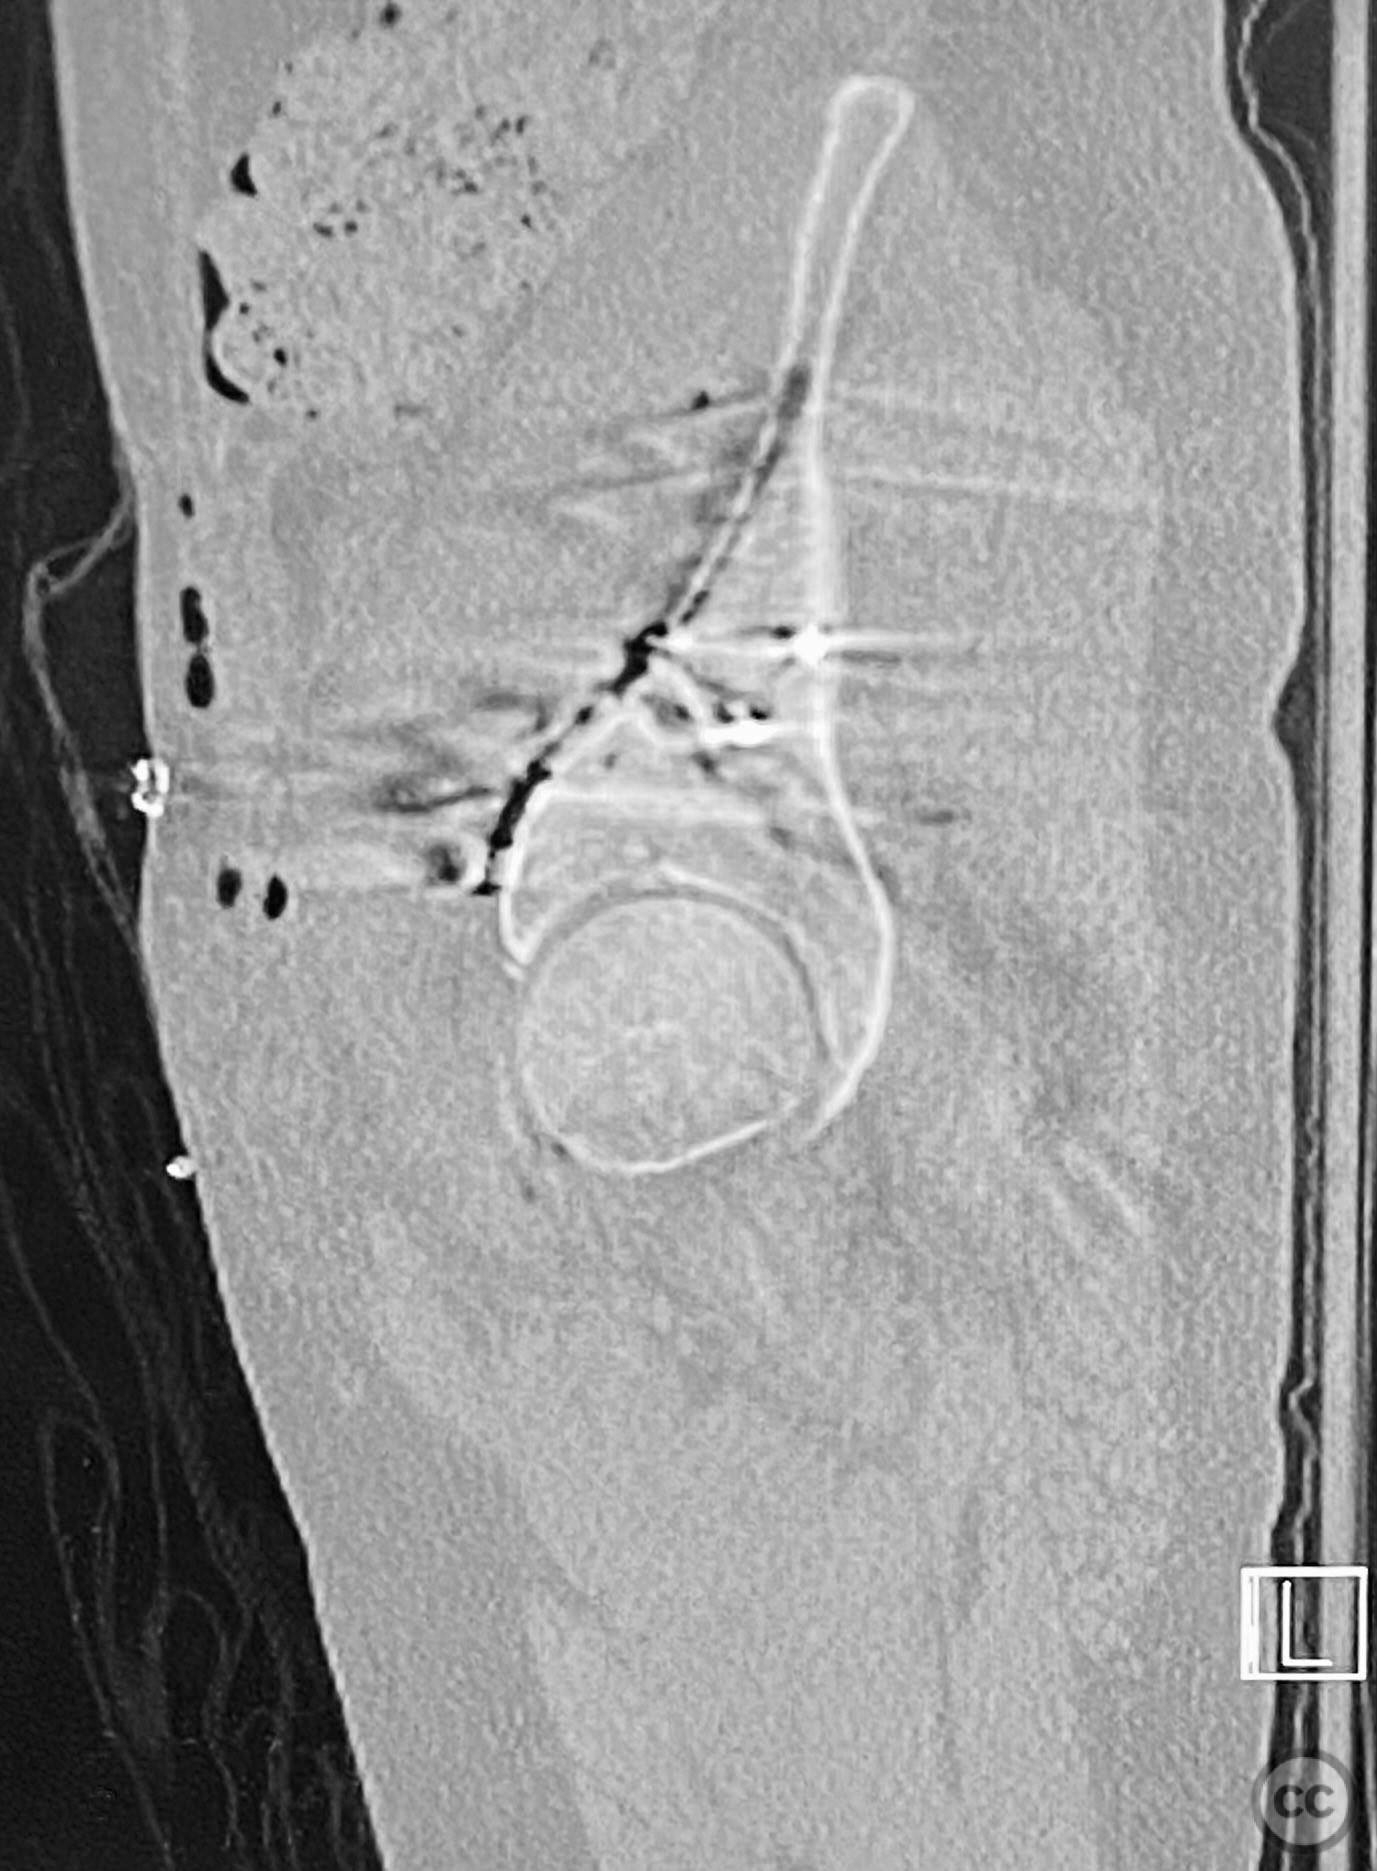

Clinical and radiological findings:  The patient sustained an acetabular fracture with a rare posterior medial dome impaction fragment, as demonstrated on AP pelvic radiographs obtained in skeletal traction. Surface renderings and axial CT images revealed multiple incomplete fracture lines, including a rhomboid-shaped cortical fragment adjacent and proximal to the anterior column/wall fragment. Coronal and sagittal reconstructions further delineated the impacted articular fragment and its relationship to the surrounding acetabular dome. The fracture pattern is classified as AO/OTA 62B3 (associated both-column fracture with dome impaction).

Planning remarks:  The preoperative plan involved an ilioinguinal approach to the acetabulum, utilizing the intrapelvic interval for initial reduction and stabilization of the posterior column with a contoured intrapelvic plate. Sequential reduction of the anterior column and direct management of the impacted dome fragment were planned, facilitated by temporary removal of the rhomboid cortical fragment.

Anatomical surgical approach:  A classical ilioinguinal approach was performed, developing the lateral, middle, and medial windows. The intrapelvic interval was used to access the quadrilateral surface and posterior column. The rhomboid cortical fragment was excised to allow direct visualization and manipulation of the impacted posterior medial dome fragment. Reduction was achieved using a spiked pusher under fluoroscopic guidance. The defect was filled with morselized allograft, and the rhomboid fragment was anatomically reduced. The anterior column was stabilized with a contoured plate. Posterior column reduction was further improved using a reduction clamp applied with one tine lateral to the anterior inferior iliac spine (AIIS) and the other on the quadrilateral surface via the middle window, followed by lag screw fixation.